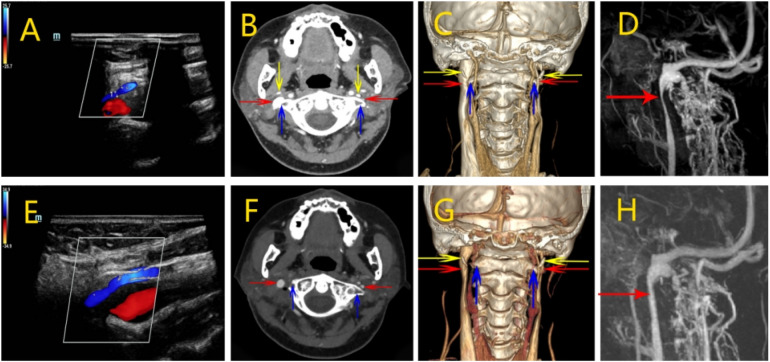

Methods: Three patients with imaging-confirmed compressive IJVS underwent Doppler ultrasound, 3D computed tomography venography, and magnetic resonance imaging. All patients receivedtargeted surgical decompression via resection of the compressive bony structures, with one patient receiving adjunctive venous stenting due to persistent flow limitation.

Results: All patients achieved significant postoperative improvement, including resolution of head noise and amelioration of associated symptoms. Imaging confirmed improved venous caliber and outflow. Notably, one patient with previous stenting failure benefited from staged decompression and re-intervention, highlighting the value of individualized management.